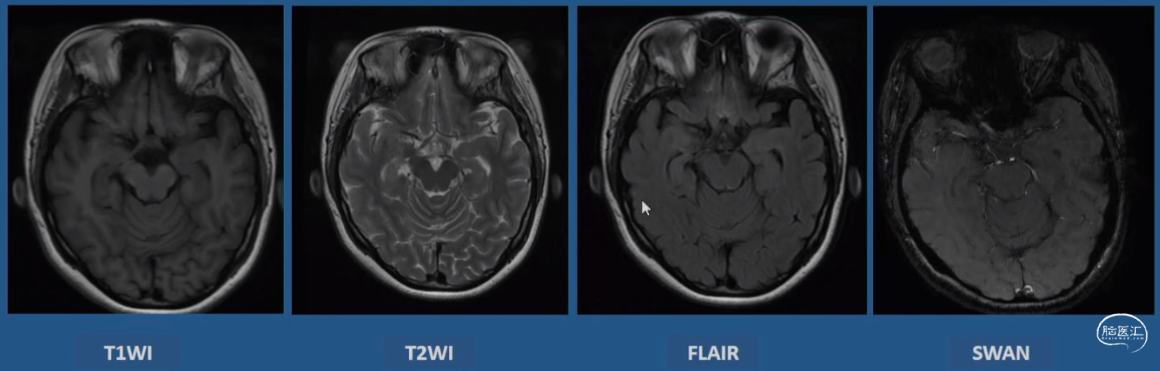

影像学表现:2018-03-05 MRI 常规MRI阴性

术后影像